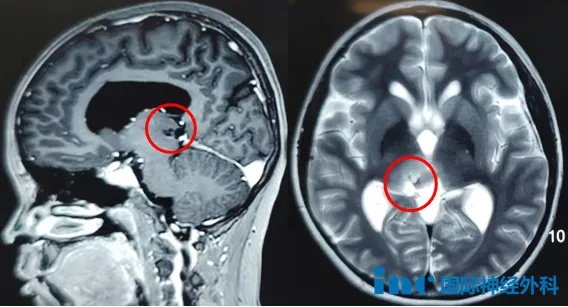

在近期巴教授2025中国行中,一位13岁的小患者新城(化名)始终牵动着大家的心弦。肿瘤边界不清,且位于神经外科中极具挑战性的“手术禁区”丘脑-中脑,手术路径狭长,可操作空间小,却遍布着无数条掌握命脉的神经和血管,手术容错率几乎为0。

父母下定决心铲除孩子成长路上的障碍,然而医生的一番话却如一盆凉水兜头而下:“肿瘤已经引发梗阻性脑积水,可以先进行三脑室底造瘘术来缓解,但由于肿瘤长在右侧丘脑-中脑,手术风险太大,不能进行肿瘤切除手术。”

根据巴教授术前的评估,新城的肿瘤切除难度较高,不仅由于肿瘤位置在脑干中脑-丘脑这一核心区域,真正的牵一发而动全身,更在于肿瘤边界不清。正常脑组织与肿瘤之间没有一条清晰的分界线,而是一个渐变的、浸润的区域,这导致手术难度极大,对术者的操作精度要求极高。